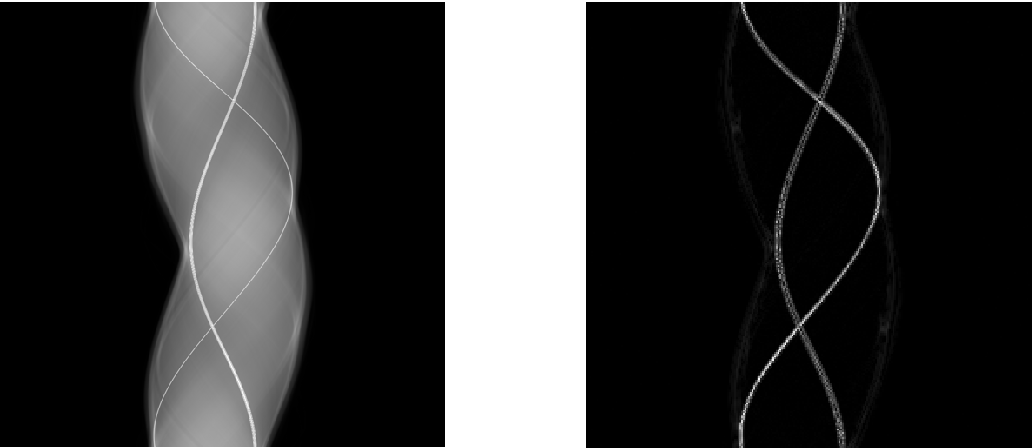

We propose a MAR method for projection-domain metal segmentation and inpainting, that uses 3D DT-CWT to find the edges of metals in the 3D sinogram. Fig. 2 shows the full workflow from 3D sinogram to metal artifact reduced reconstruction. The method is explained in detail below.

revealing the locations in the 3D sinogram space corresponding to the largest coefficients. See the 2nd row of Fig. 3 for an illustration of the resulting point cloud for two different 3D sinograms. Then, the result is binarized to by:

Voxels that fail this connectivity test are removed as isolated noise. By iterating this procedure, the remaining structures exhibit coherent propagation across slices, resembling the flow of information in a CBCT sinogram. The resulting values form a point cloud that corresponds to the singular support of the metal traces in the 3D sinogram space.

Next, we convert , which contains points located on metal boundaries, into a full binary mask for metal segmentation. Since the extracted boundary may not form a closed surface, we complete it using standard morphological operations [21]. In particular, we apply morphological closing, which consists of a dilation followed by an erosion using the same structuring element .

After the boundary has been closed, the interior is filled using a flood-fill operation (MATLAB’s ’imfill’ function). The resulting binary mask represents the segmented metal regions in the 3D sinogram (see the third row of Fig. 3).

4.3 Sinogram inpainting and metal-free reconstruction

Using the metal mask , voxels corresponding to metal structures are segmented from the original 3D sinogram , yielding a metal-removed sinogram . See the fourth row of Fig. 3. The missing regions are filled using harmonic inpainting by solving the discrete Laplace equation within the masked region subject to Dirichlet boundary conditions prescribed by the surrounding known pixel values using MATLAB’s ’regionfill’ function.